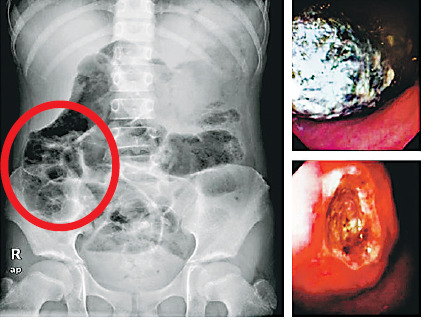

香港中大儿科教授韩锦伦表示,约一两年前,一名9岁女孩随母亲到威院求诊,她过去身体良好,但忽然肚痛及呕吐达3周,曾一日呕四五次,体重在6周内下跌两公斤,甚至开始贫血,送院照内窥镜发现其左边胃积聚两大团头发,长度约16厘米,甚至伸延至肠道,其胃部周边更有2至3平方厘米的溃疡,医生为她取出该两团头发后才逐渐痊愈。

韩锦伦解释,该女童来自内地,自3岁在香港定居,患“巨肠症”易致肠塞,曾多次因各种病痛出入威院,并住进深切治疗部,相信是长期插胃喉关系,令她趁机吃下不少用作封喉的白色胶布。威院医生为她开刀取出异物,“当时夹了20次才夹出了六成垃圾(即胶布)”,并要修补肠脏破洞及脓肿。该女童亦感染肺炎链球菌引发腹膜炎,做手术及用药后已痊愈。